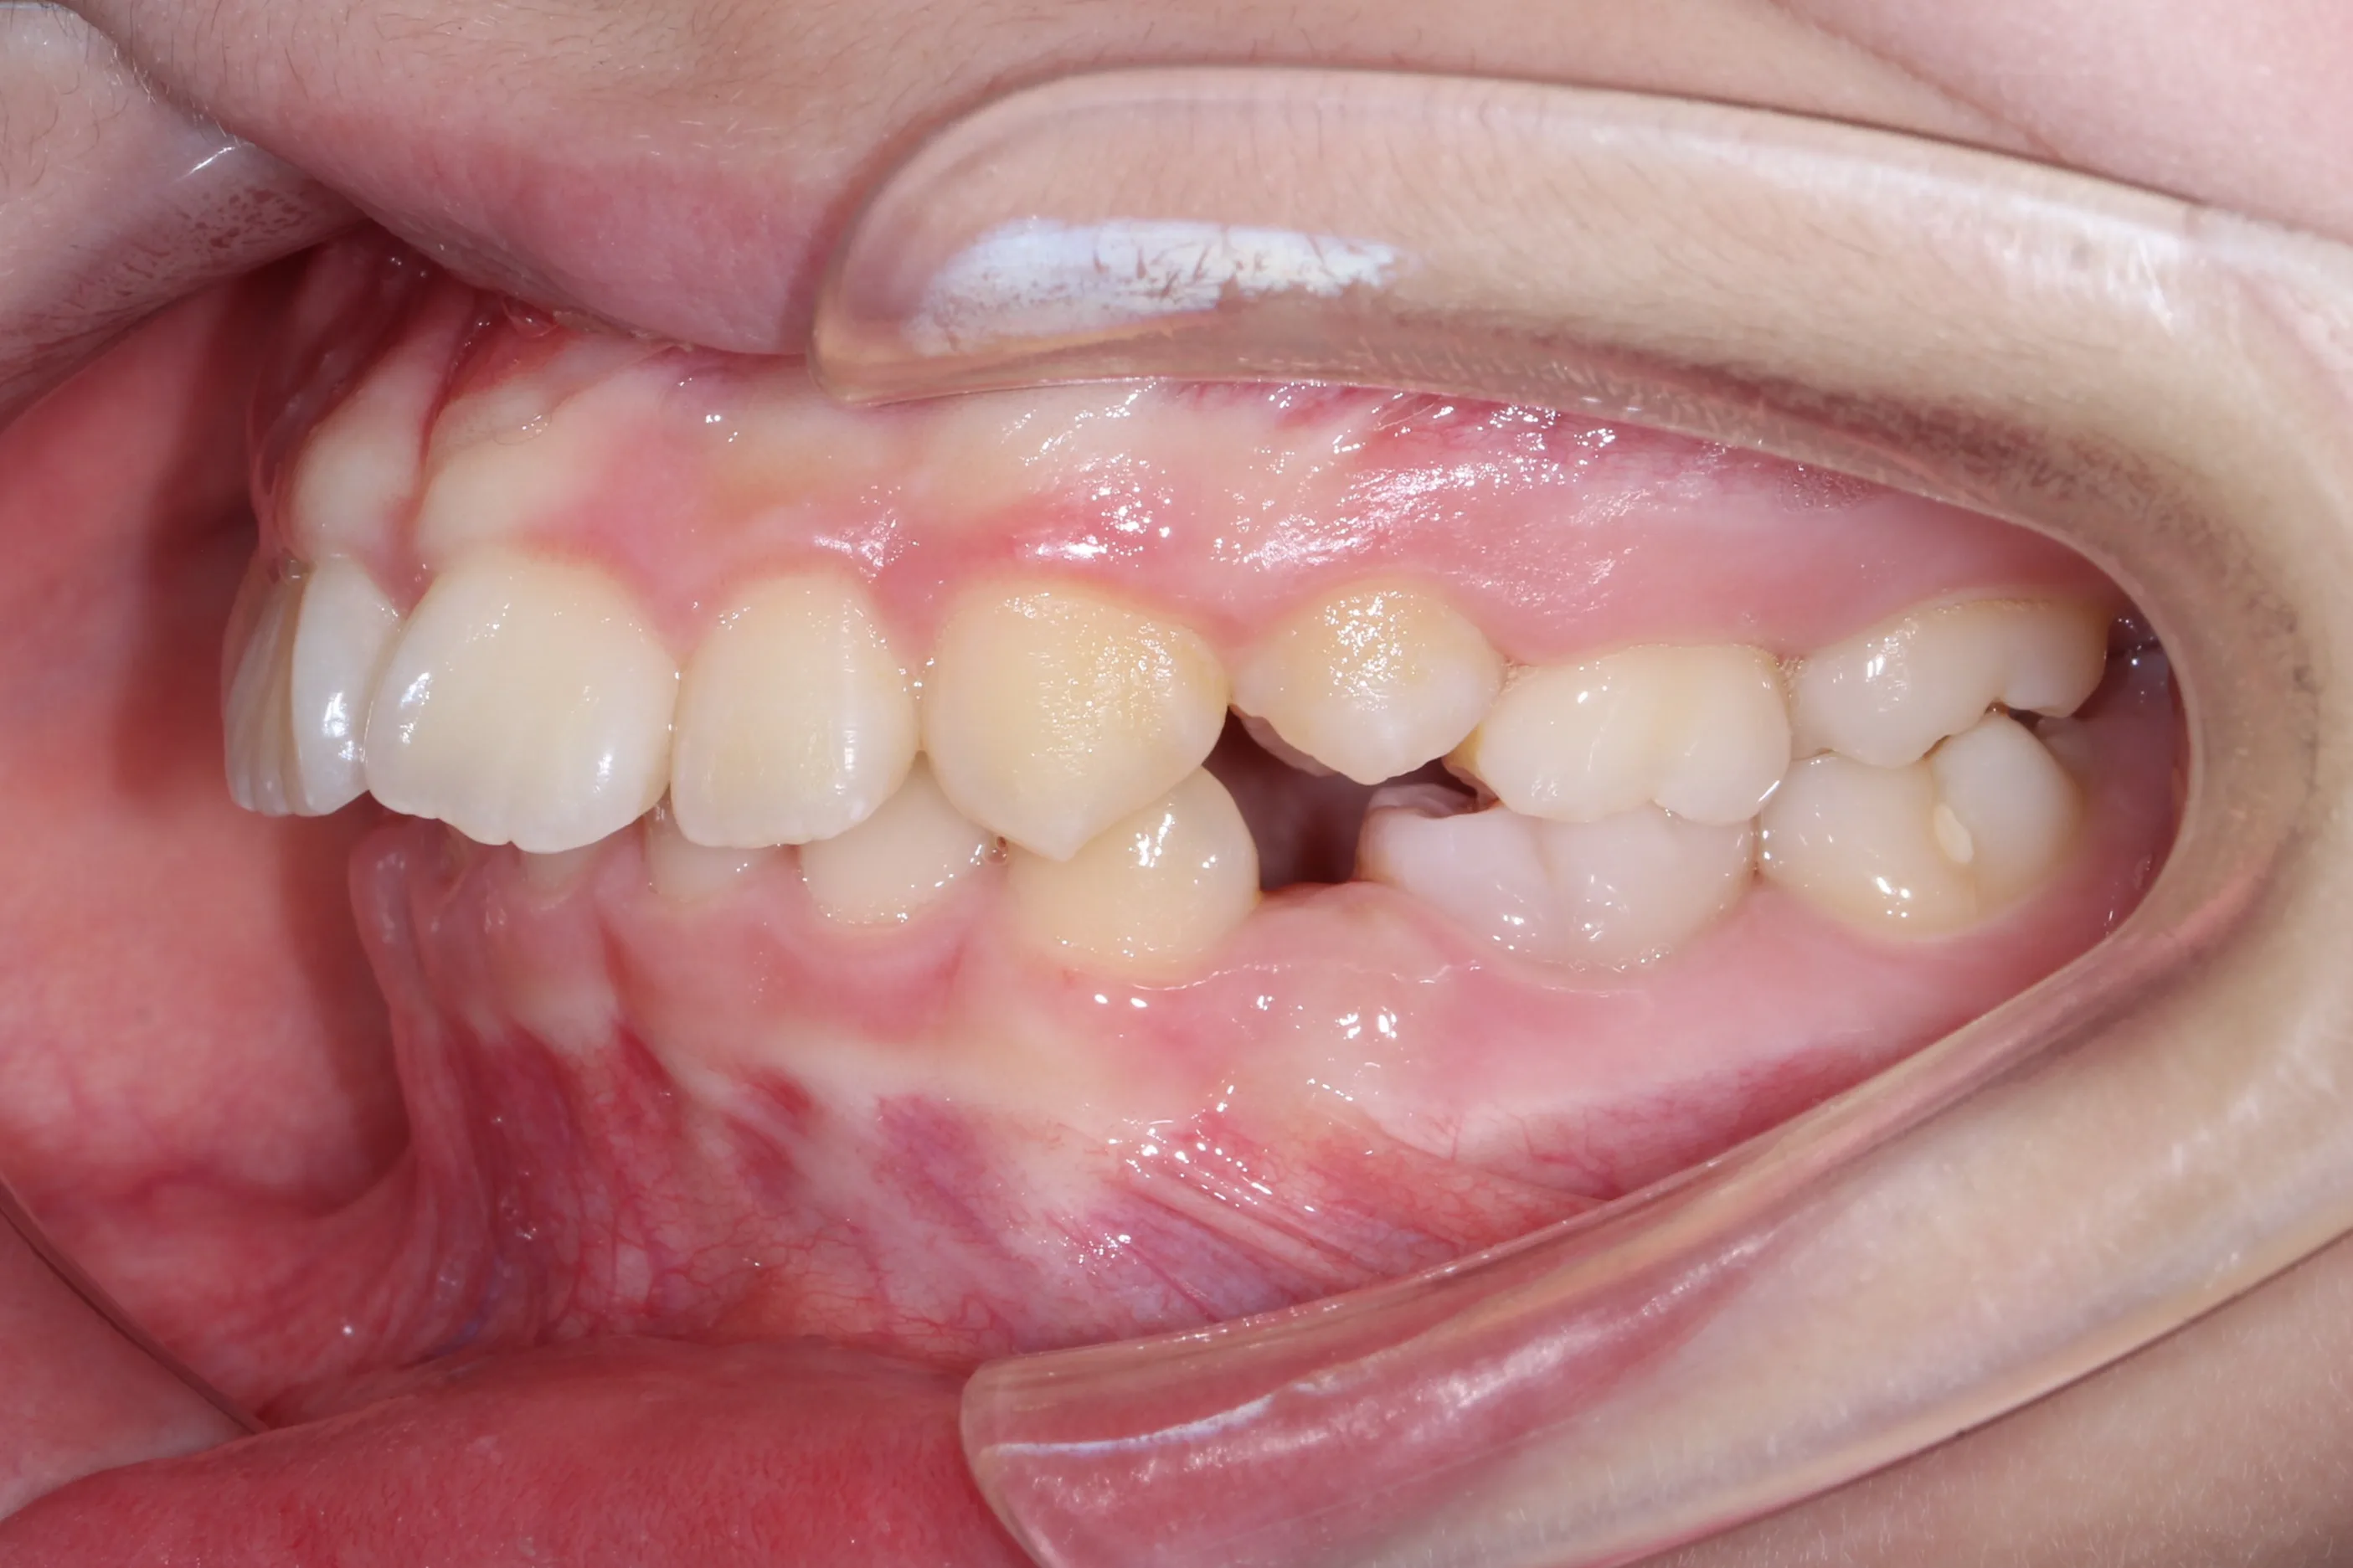

만 11세 환자분께서 튀어나온 앞니와 다물어지지 않는 입술 때문에 내원하셨습니다. 검진 결과 상악 전돌을 동반한 2급 부정교합(Class II malocclusion) 상태였으며, 아래턱의 성장이 다소 부족하여 골격적인 조화가 필요한 상황이었습니다.

이번 치료에는 인비절라인 퍼스트(Invisalign First)에 하악 전방 견인(Mandibular Advancement, MA wing)을 추가하여 치료를 진행하였습니다. 성장기라는 시기적 특성을 적극 활용하여 아래턱의 점진적인 성장을 유도하고, 과도한 상악 전치부 돌출을 개선하는 데 치료의 핵심 전략을 두었습니다.

2년 7개월의 치료 과정을 거치며 환자분의 협조도 덕분에 안모 프로파일과 교합이 안정적으로 개선되었습니다. 성장기라고 해서 무조건 교정이 어려운 것은 아닙니다. 적절한 시기에 맞춤형 장치를 선택한다면 골격적 불균형을 효과적으로 바로잡을 수 있습니다.